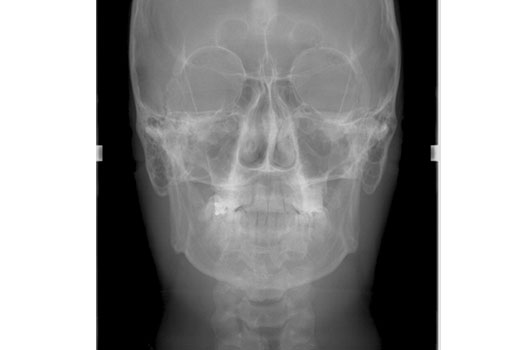

CEFÁLICA FRONTAL

Realizado para Ortodoncia y Cirugía Máxilo Facial,  el estudio cefalométrico  se realiza sobre esta radiografía, el cual consiste en hacer trazos que determinan ejes de crecimiento, posición de los maxilares, inclinación de los dientes, tamaños de los huesos, desviaciones y asimetrías dentales y esqueletales, etc. Valores que permitirán un diagnóstico y plan de tratamiento en estas especialidades.